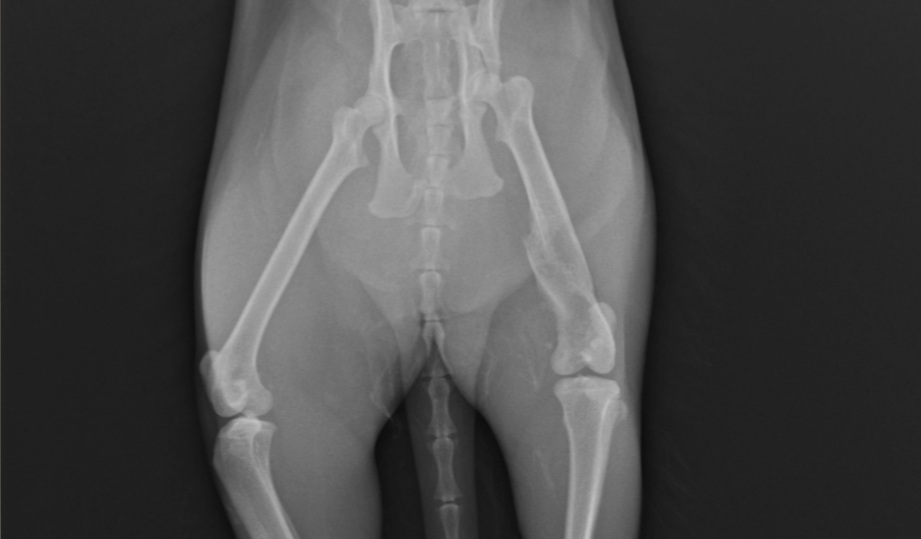

Trzy lata temu odłowiłam na osiedlu do sterylizacji dziką około 2letnią kotkę, która nazwaliśmy LUSI. Okazało się, że ma gorączkę, zapalenie płuc i inne przypadłości kota dziko - żyjącego. Z uwagi na konieczność leczenia, LUSIA zamieszkała z nami. Bardzo szybko zaadoptowała się do nowych warunków, więc została z nami. W tym roku zrealizowałam moje marzenie i przeprowadziłam się do mieszkania z ogródkiem. W trakcie prac wykończeniowych, przez nieuwagę pracownika wystraszona uciekła. Blisko 3 miesiące poszukiwałam ją bezskutecznie, aż do 18 marca Tego dnia szłam do domu i kotka słysząc mój głos, wyczołgała się z krzaków pod moje nogi ciągnąc za sobą tylną łapkę. Od razu udałam się do weterynarza i cios w serce... Okazało się, że LUSI została brutalnie, z wielką siłą potrącona przez samochód kilka tygodni wcześniej i pozostawiona w olbrzymim bólu i cierpieniu. Kotka po tym zdarzeniu zdziczała, ale nie dając za wygraną udałam się do znanego i polecanego specjalisty chirurga – ortopedy. Weterynarz zaleciła dalszą diagnostykę neurologiczną, leczenie farmakologiczne i dała nadzieję na wyzdrowienie kotki po zoperowaniu jej pękniętej miednicy i łapki. Niestety z uwagi na trudną sytuację finansową, nie jestem w stanie sama podołać tym kosztom. Bardzo proszę o wsparcie, abym mogła ulżyć kotce w cierpieniu.